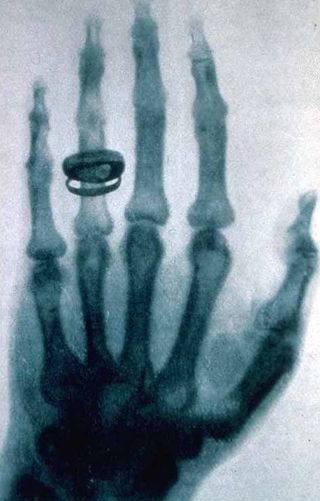

X-ray of a hand. X-rays are a common medical test. | |